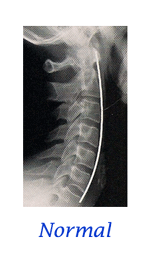

Stages of Spinal Degeneration

When it comes to the spine, the average person’s only interest is with PAIN. Statistics claim that each of us will be disabled with low back pain at least twice in our lives. We may, on average, only miss a couple days work, but many people find back pain to be a lifelong “challenge”. For too long, and too often, the general public has been coerced into thinking that surgery is the only answer for a diagnosis of “slipped disc”. But what is a “slipped disc”? Most people think it is like biting into a tuna sandwich and having all the tuna go out the backside. Oops! That must be really bad! Then again, you may have been told that your diagnosis is a “bulged disc”, “protruding disc”, “herniated disc”, “degenerating disc”, “Fragmenting disc” or maybe “degenerative disc disease”. How confusing can these disc problems be? VERY CONFUSING! . . . continue with Do You Have a "Slipped Disc"?